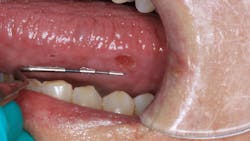

Clinical assessment revealed overall red, inflamed tissue throughout the oral cavity. Most notably present were large, ulcerlike lesions on the right and left lateral borders of the tongue (figures 1 and 2). The edges were well-defined and the red center slightly concave and very tender to palpation. Further, the vestibular tissue, upon the slightest touch, sloughed and hemorrhaged easily. Angular cheilitis was observed, and opening was painful (figure 3).